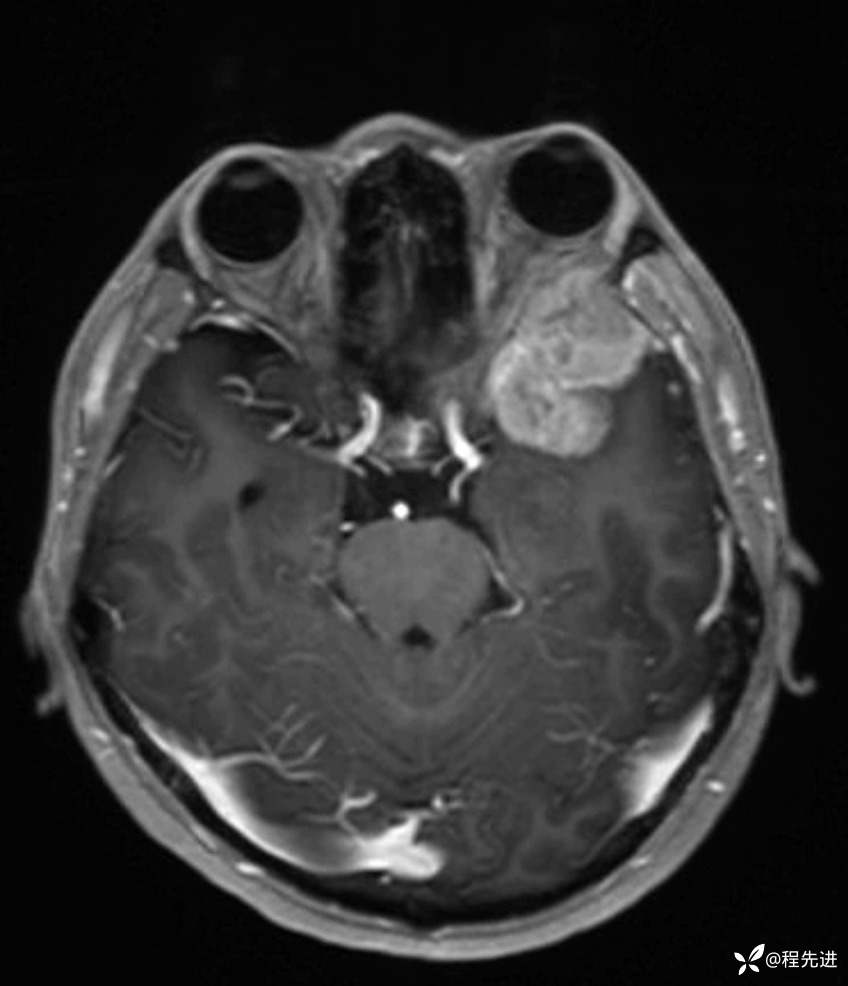

MR平扫+增强:

T1增强: